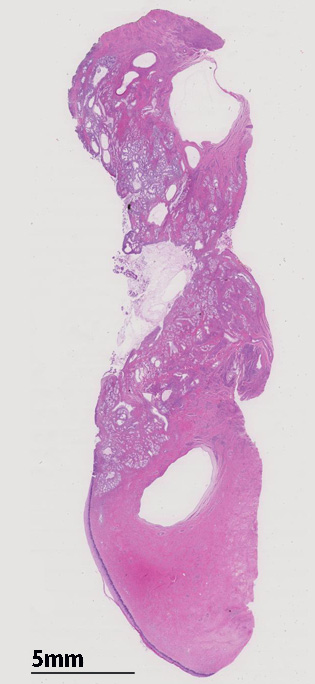

LEGHloupe01.jpg

子宮頚管腺に類似した高円柱上皮よりなる腺管の著明な増生を認める。これらは大型で拡張した導管様腺管と,それを囲繞するように配列する分葉状構造をしめす小型腺管からなり, 嚢胞状に拡張した腺管も随所に認められる。最深部にみられる腺上皮は, 嚢胞状に拡張した腺管の一部と考えられる。

loupe像では, 拡張した導管を中心に高円柱上皮からなる腺管が分葉状に配置する所見が認められる。